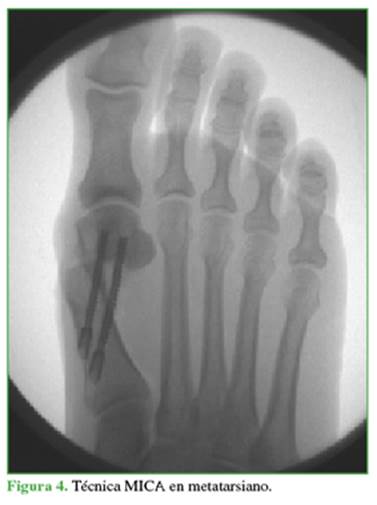

Resumen de la técnica MICA

Asocia una osteotomía en Chevron percutánea a través de un portal medial distal metatarsiano con una fresa Shannon larga y de forma extrarticular; y una osteotomía percutánea de Akin con fresa Shannon corta. El corte metatarsiano debe ser orientado inicialmente con un ángulo plantar de 10°, y luego realizar las dos ramas (plantar y dorsal). Se estabiliza la osteotomía metatarsiana luego del deslizamiento lateral de la cabeza, con dos tornillos canulados doble rosca largos paralelos, desde la metáfisis proximal del metatarsiano hacia la cabeza del mismo hueso (Figura 4); y eventualmente la Akin con un tornillo canulado.